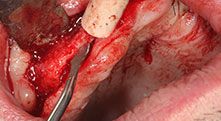

Piezomed B6

La cresta alveolar se ranura en ambos lados mediante piezocirugía (inserto: Piezomed B6). La implantación se realiza en la misma intervención y el hueso que rodea el implante se estructura además con una regeneración ósea guiada (GBR).

Implantes

Los cuatro implantes se encuentran in situ tal como estaba planeado. Los molares distales del maxilar superior sirven además para fijar la prótesis con base reconstruida, que se monta un mes después de la implantación.